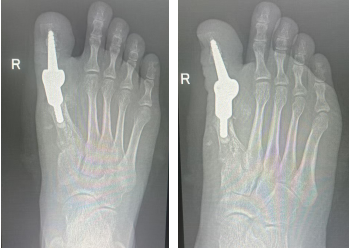

二期右足行3D打印个体化跖趾关节重建方案:通过CT获取足部三维数据,1:1还原骨骼缺损与畸形结构,数字化设计完全匹配患者解剖的定制假体,再通过金属3D打印技术制造专属假体,真正实现“量骨定制、精准植入”。

定制假体

手术过程顺利,术中定制假体与骨床完美贴合,畸形彻底矫正。术后患者关节活动保留,步态恢复理想,康复进程显著快于传统手术。